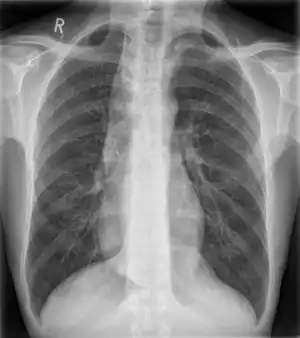

Some mediastinal structures on a chest radiograph.

Widened mediastinum in a patient with achalasia

Widened mediastinum/mediastinal widening is where the mediastinum has a width greater than 6 cm on an upright PA chest X-ray or 8 cm on supine AP chest film.[11]